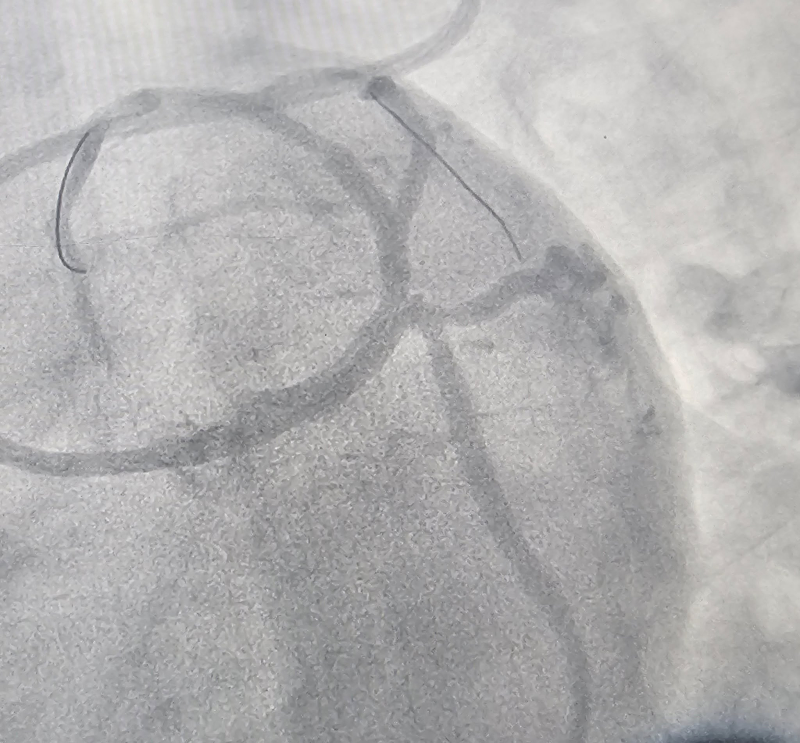

Các bác sĩ Khoa Tim mạch – Bệnh viện Bãi Cháy vừa can thiệp thành công cho bệnh nhân nam 34 tuổi bị nhồi máu cơ tim cấp. Kết quả chụp mạch vành cho thấy bệnh nhân hẹp 90% động mạch liên thất trước (LAD) và nhánh chéo 1 (Diag1). Người bệnh được xử trí kịp thời bằng kỹ thuật can thiệp đặt stent chỗ chia đôi (Mini-Crush), tái thông dòng chảy mạch vành, giúp bảo toàn chức năng tim.

Thạc sĩ, bác sĩ Đinh Danh Trình, Trưởng khoa Tim mạch, Bệnh viện Bãi Cháy cùng ê kíp đang tiến hành chụp và can thiệp đặt stent mạch vành cho bệnh nhân.

Hình ảnh: trước và sau khi can thiệp